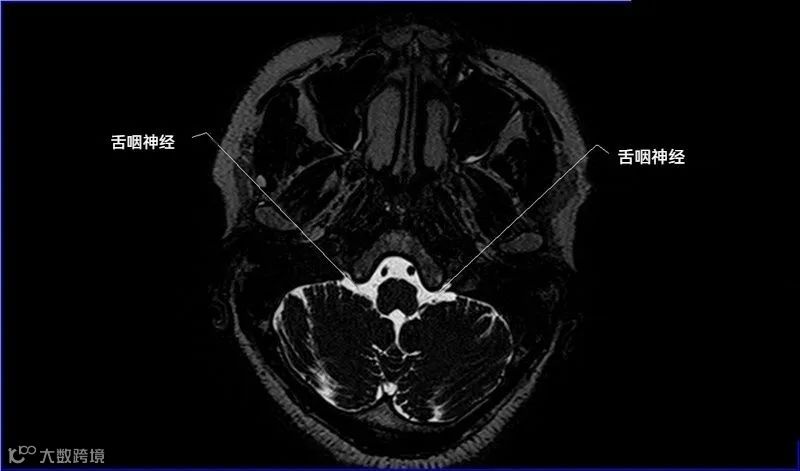

十二对脑神经口诀

一嗅二视三动眼,四滑五叉六外展,

七面八听九舌咽,迷走及副舌下全。